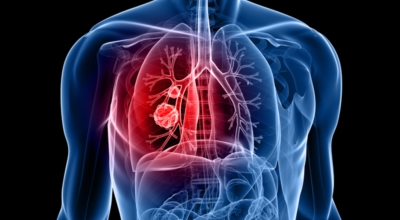

폐에 발생된 악성 종양을 말하며 오랜 기간 흡연해온 남성들에서 발병률이 높고 요즈음 각종 환경적인 요인의 영향과 간접흡연으로 흡연하지 않는 여성에서도 많이 발생하고 있습니다. 증상을 느껴 병원을 찾았을 때는 수술하기 늦은 경우가 많아 사망 가능성이 매우 높은 암입니다. 폐 자체에서 발생하거나 다른 장기에서 발생된 암이 폐로 전이되어 발생하기도 하고 특별한 초기 증상이 없는 경우가 많고 암이 진행된 후에도 공통적인 감기 증상인 기침과 가래 외의 특이 증상이 나타나지않아 증상만으로는 진단이 쉽지 않습니다.

폐암 역시 다른 암들과 마찬가지로 조기 발견 및 치료가 매우 중요하므로 일상 속에서 폐암 초기증상을 간과하지 않도록 주의를 기울여야 합니다. 따라서 장기간의 흡연, 간접흡연에 노출됐거나 일반적인 때 폐 기능이 좋지 않고 호흡기 질환에 잘 걸리는 예민한 편이라면 폐암 증상에 대하여 잘 알아뒀다가 이상이 있다고 생각되면 최대한 빨리 전문의를 찾아 정확한 검진을 받아보는 것이 좋습니다.